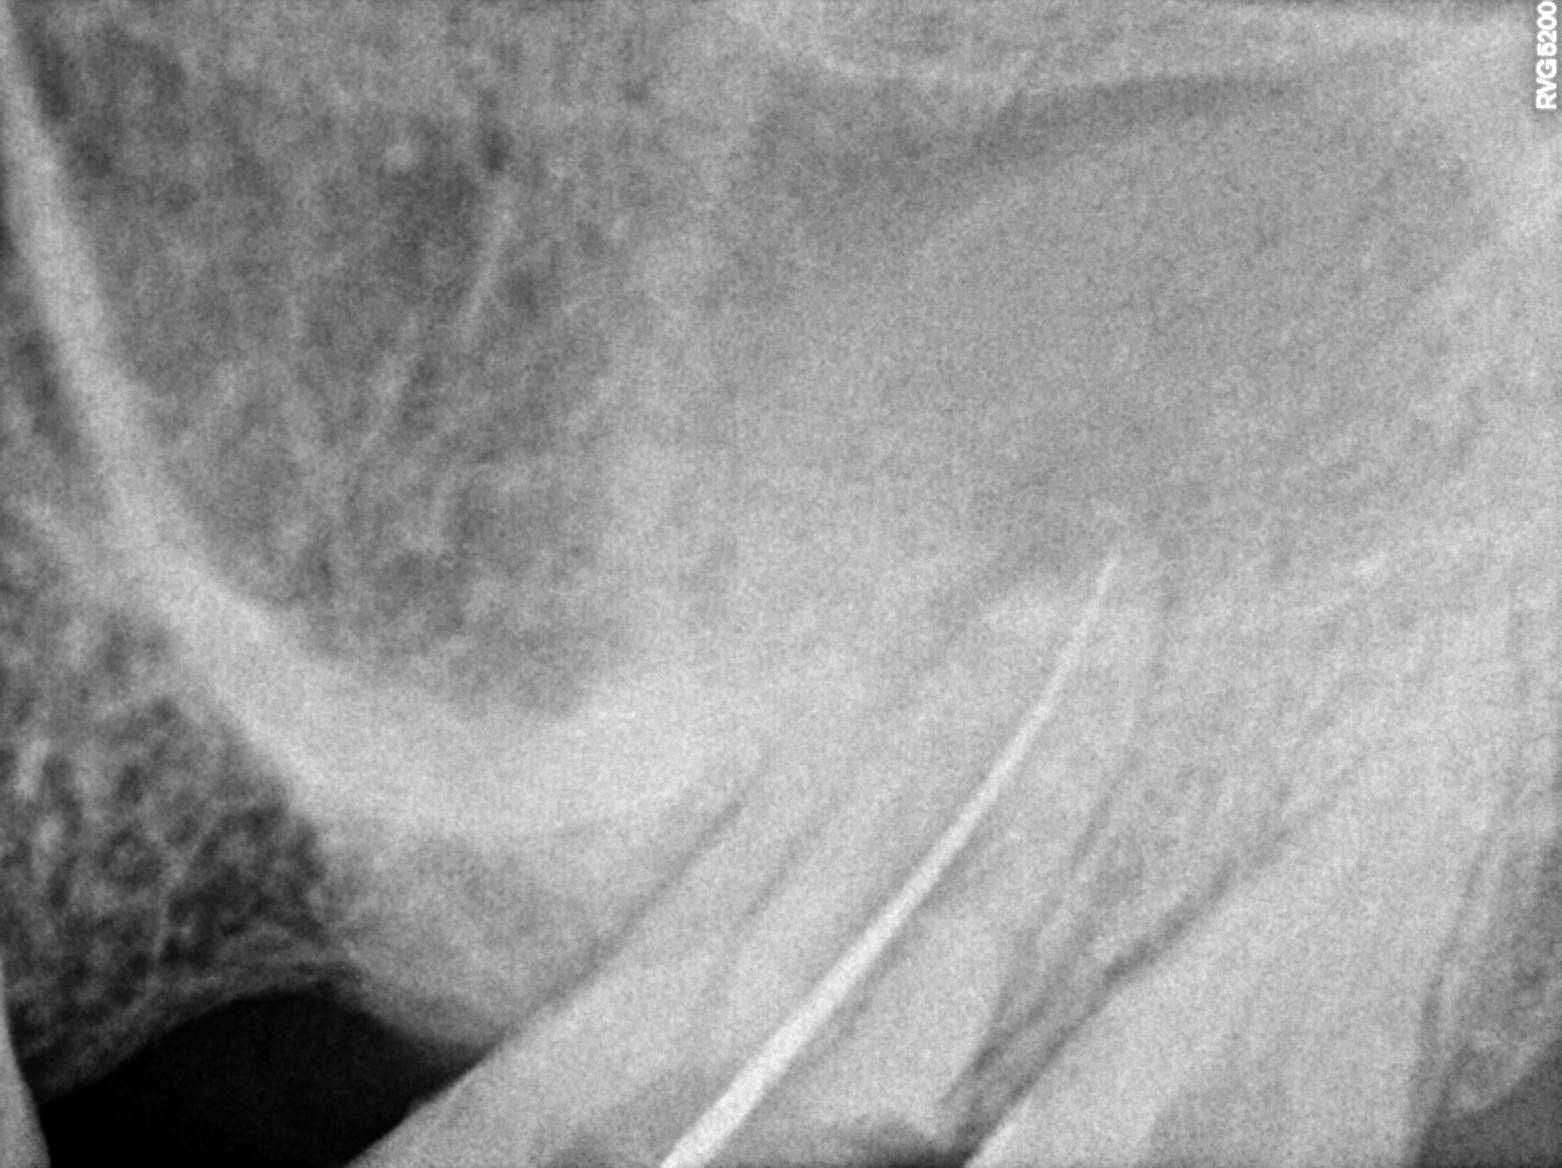

Dental Radiographs FHIR: DocumentReference · LOINC 24641-7

xray_1772815944_1.jpg

24641-7